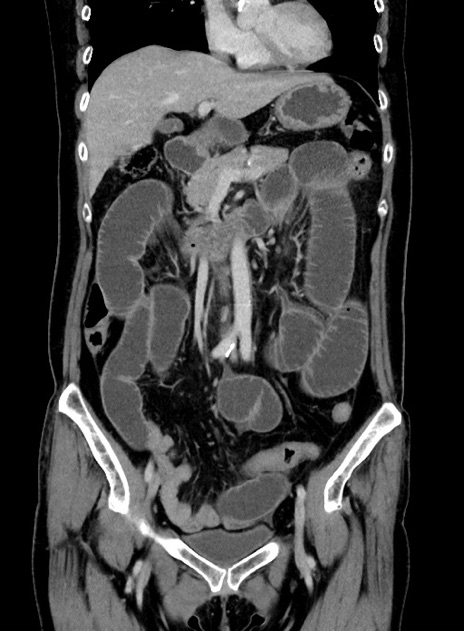

横断像

【症例】 60歳代女性

【主訴】むかつき、みぞおちの痛み

【現病歴】3日前よりむかつきがあり、食事がとれない。

【既往歴】糖尿病

【身体所見】発熱なし、心窩部圧痛軽度あるも、腹膜刺激症状なし。

【データ】WBC 7400、CRP 1.92